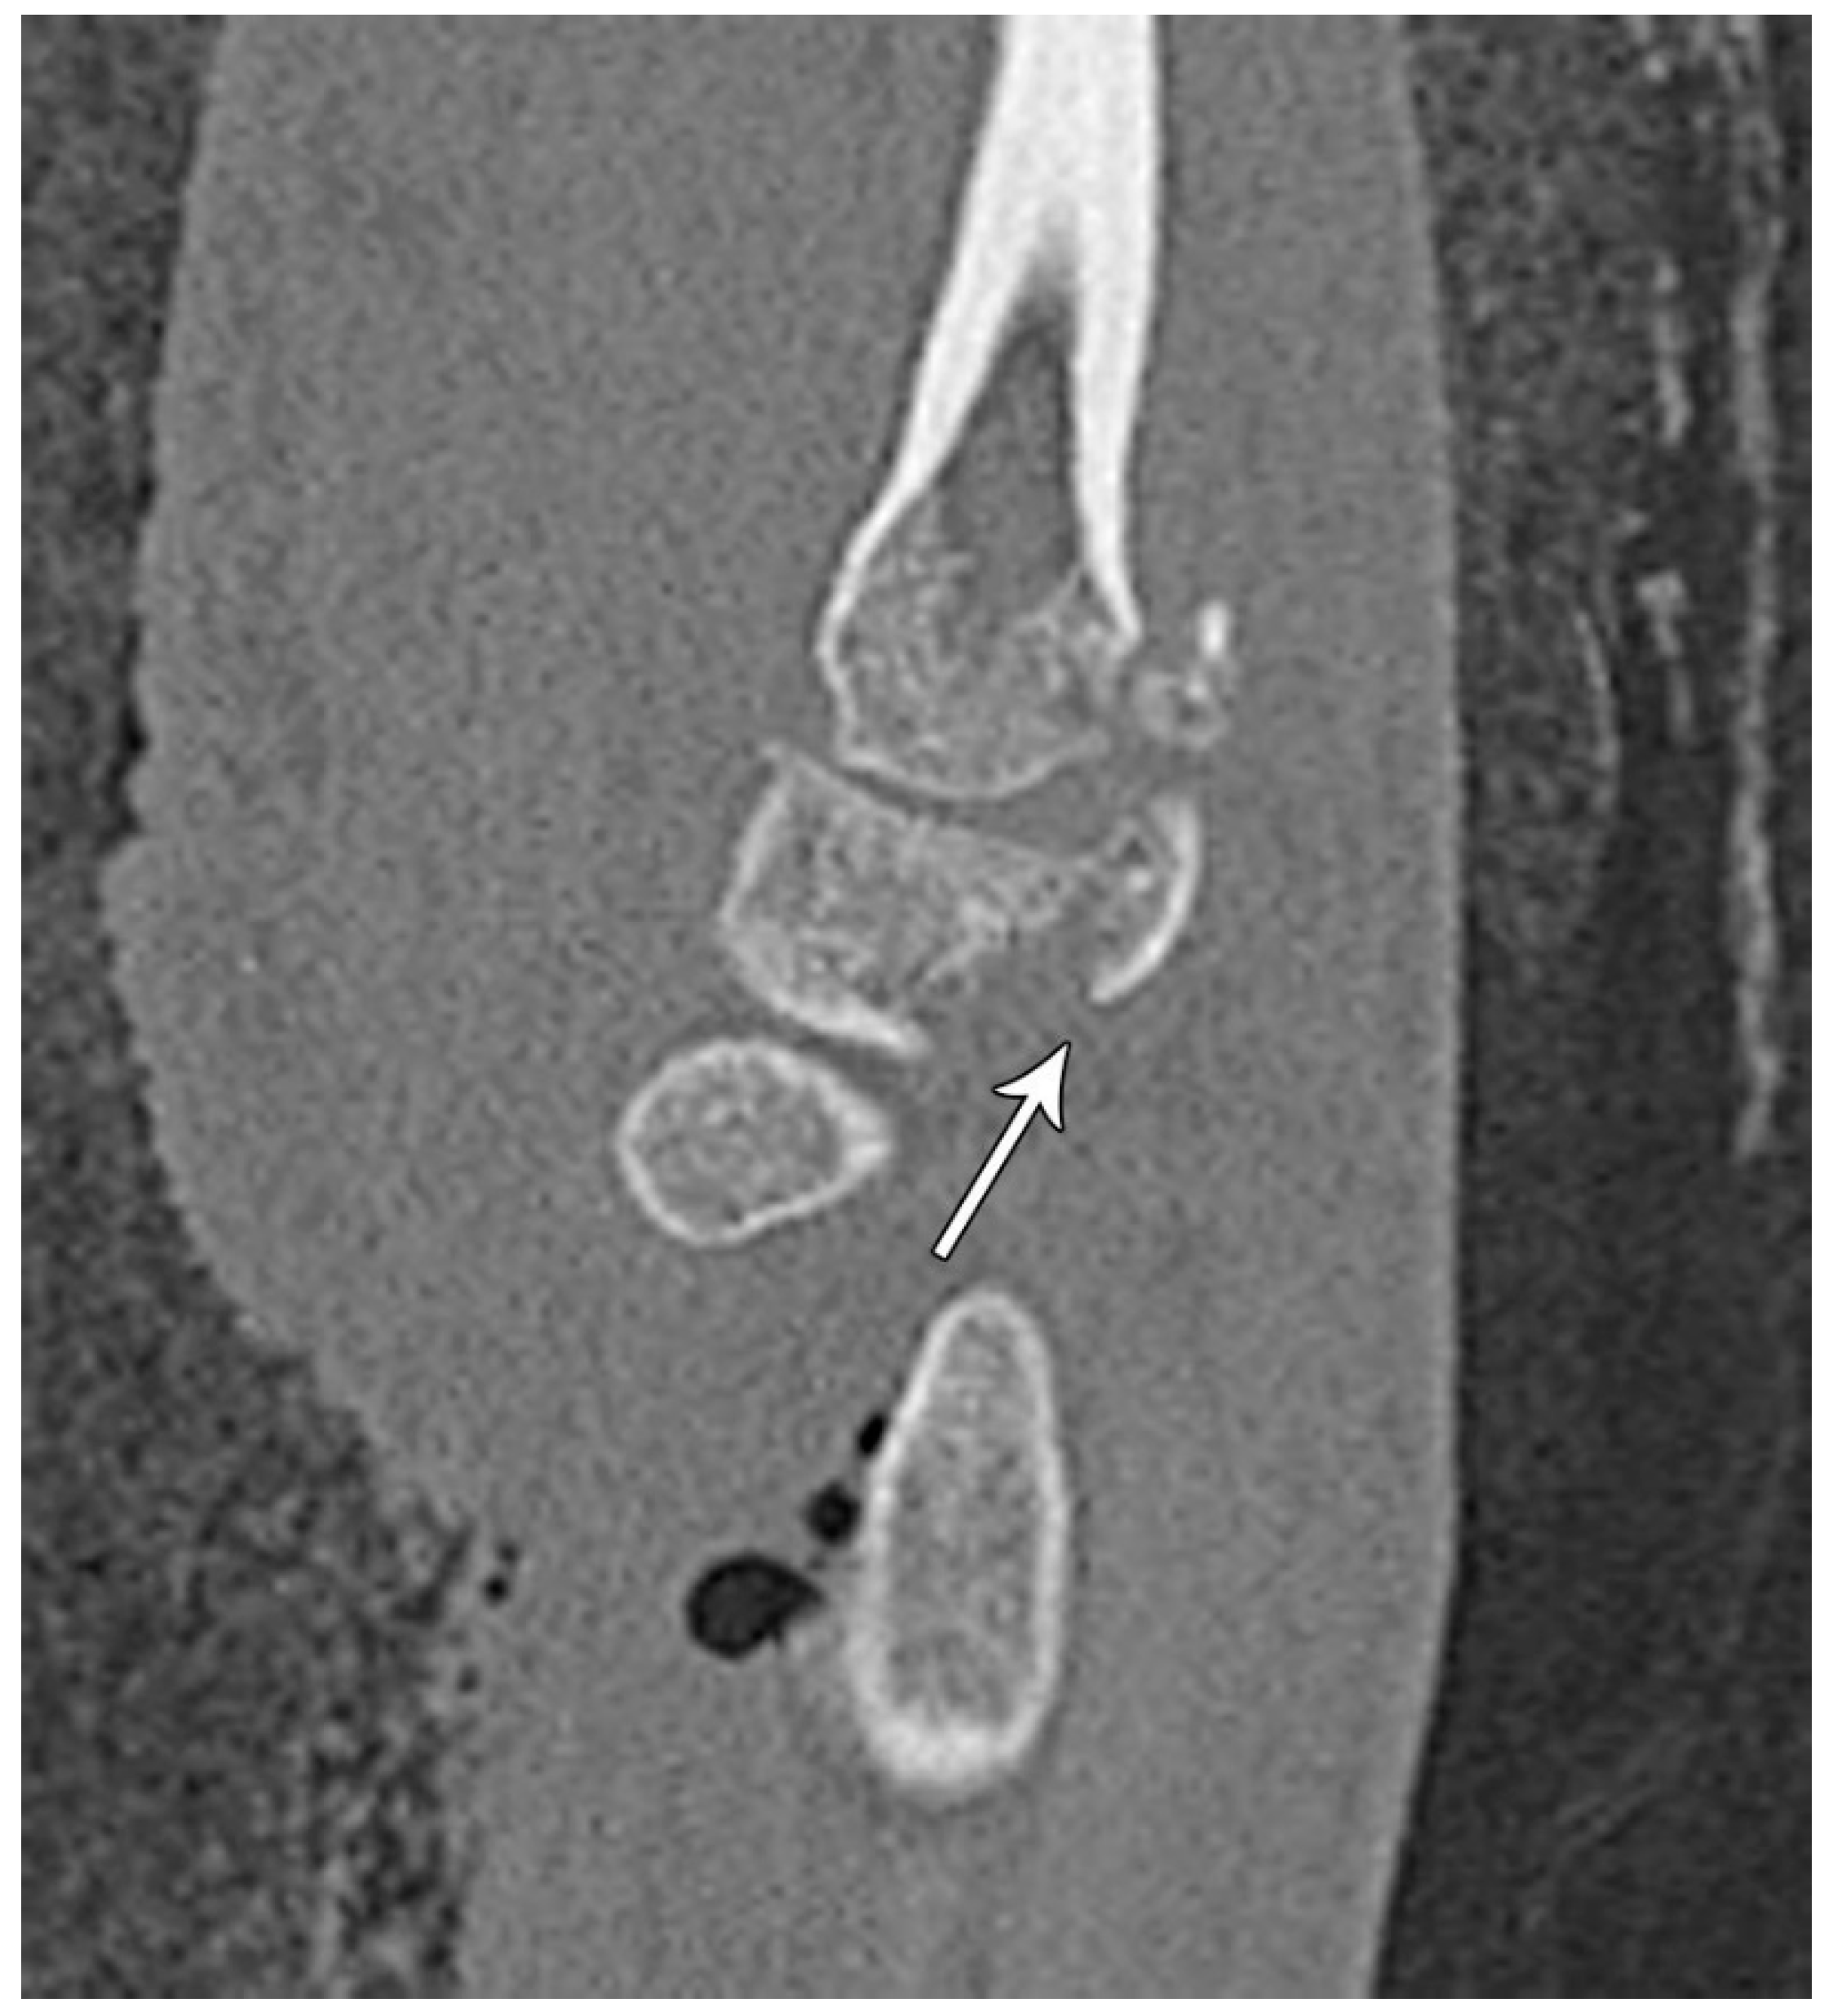

Figure 16. Sagittal reformatted CT of the wrist showing transarticular lunate fracture (arrow).